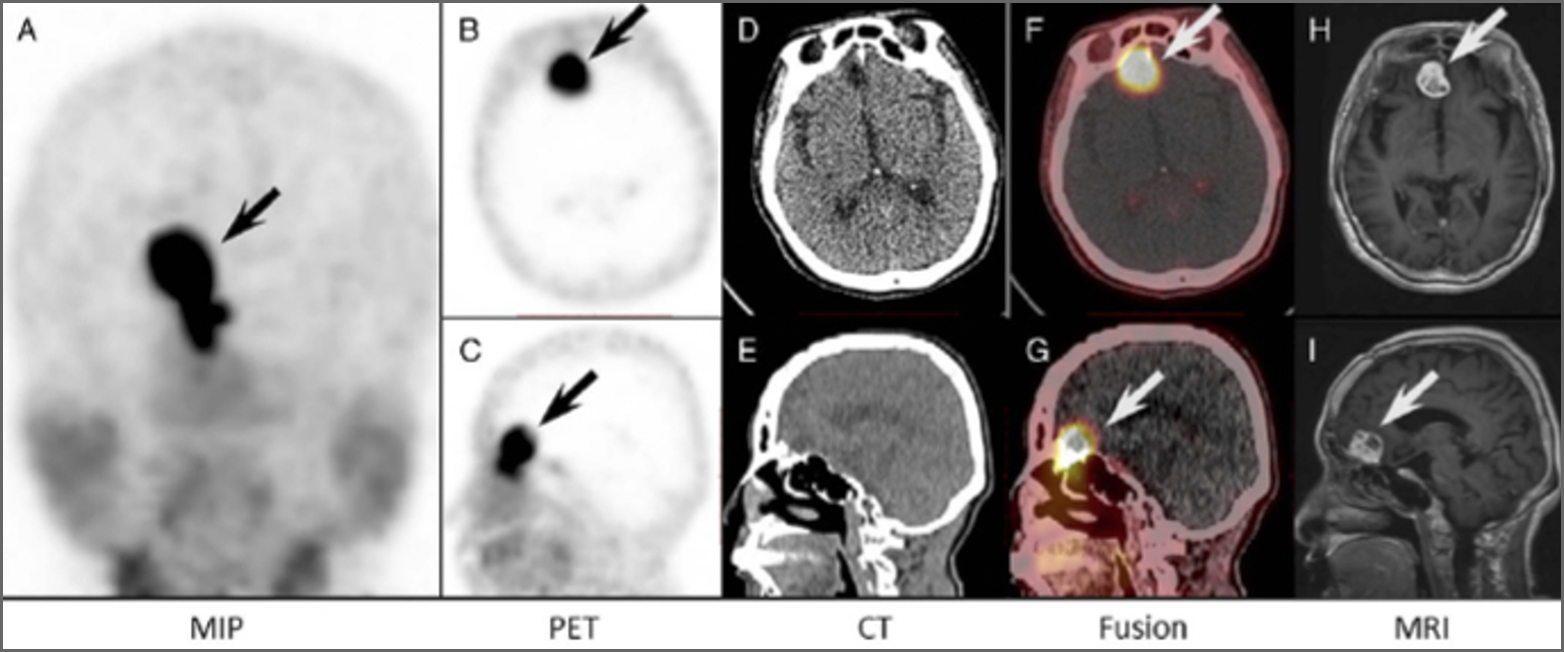

Chemokine receptor -4 targeted PET/CT with68Ga-Pentixa for in assessment of newly diagnosed multiple myeloma:comparison to 18F-FDG PET/CT

Qing qing Pan · Xinxin Cao · Yaping Luo · Jian Li ·JunFeng · FangLi